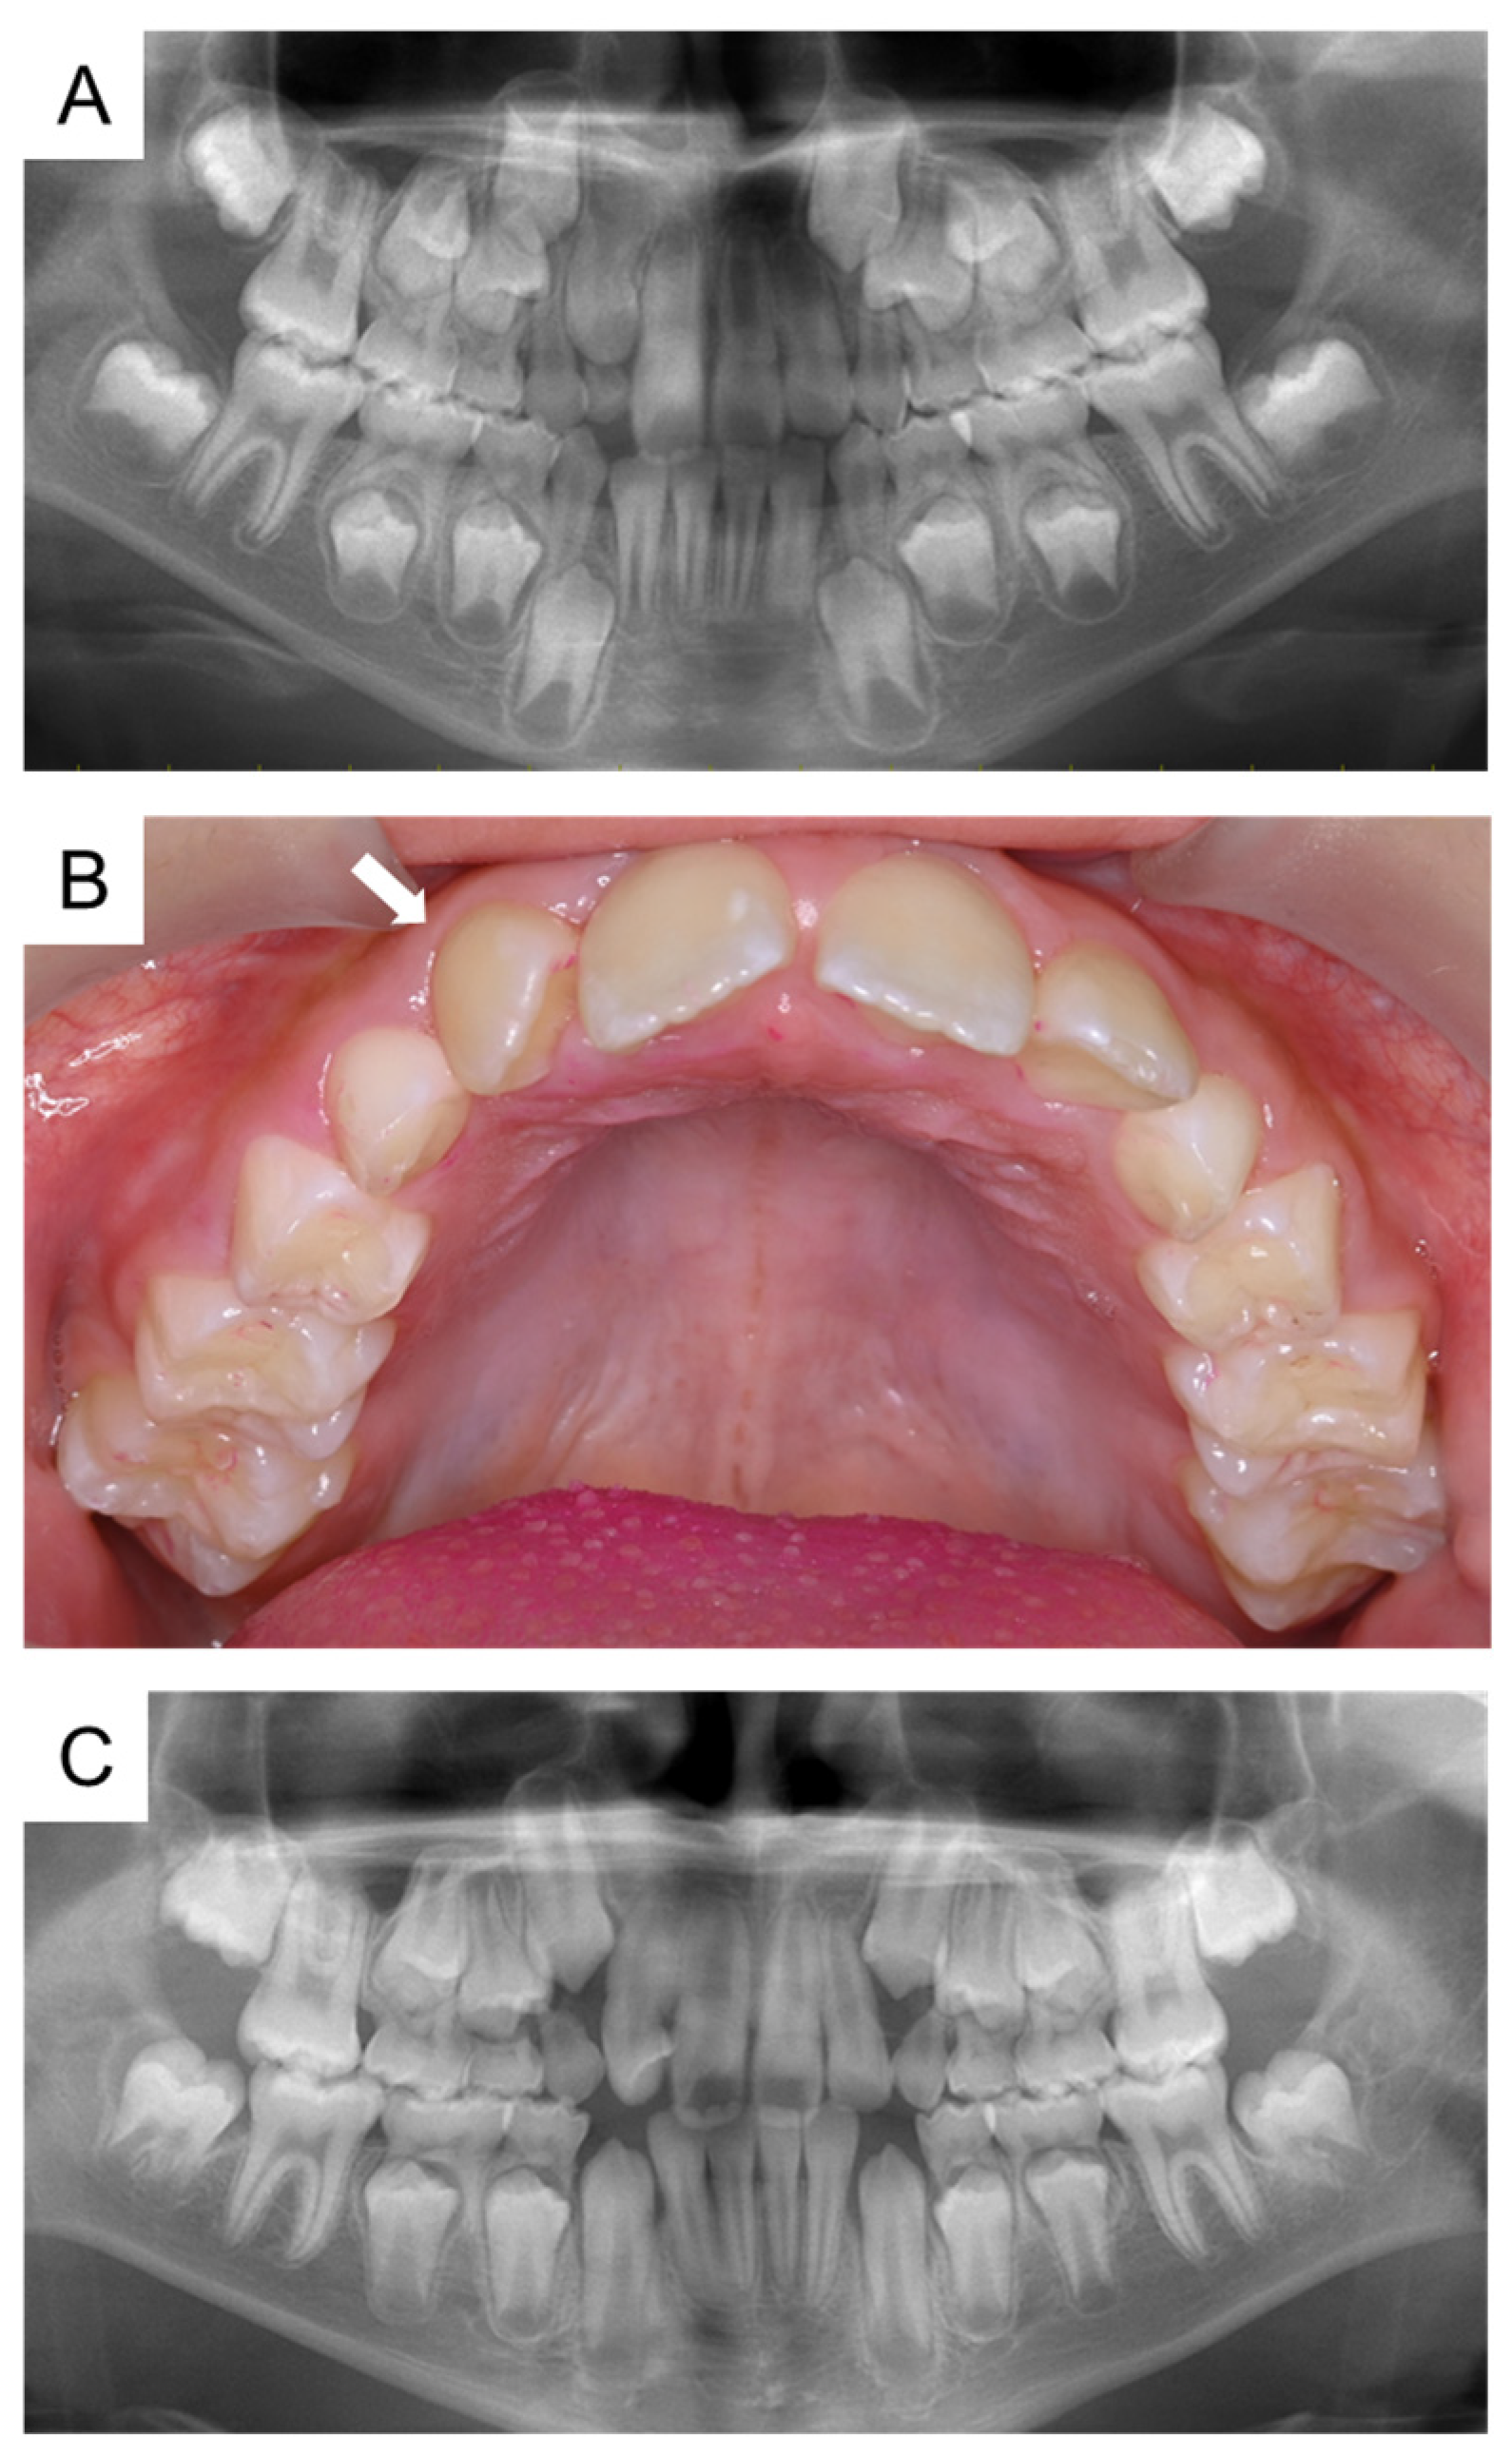

2. Case Presentation

5.2. The Present Case